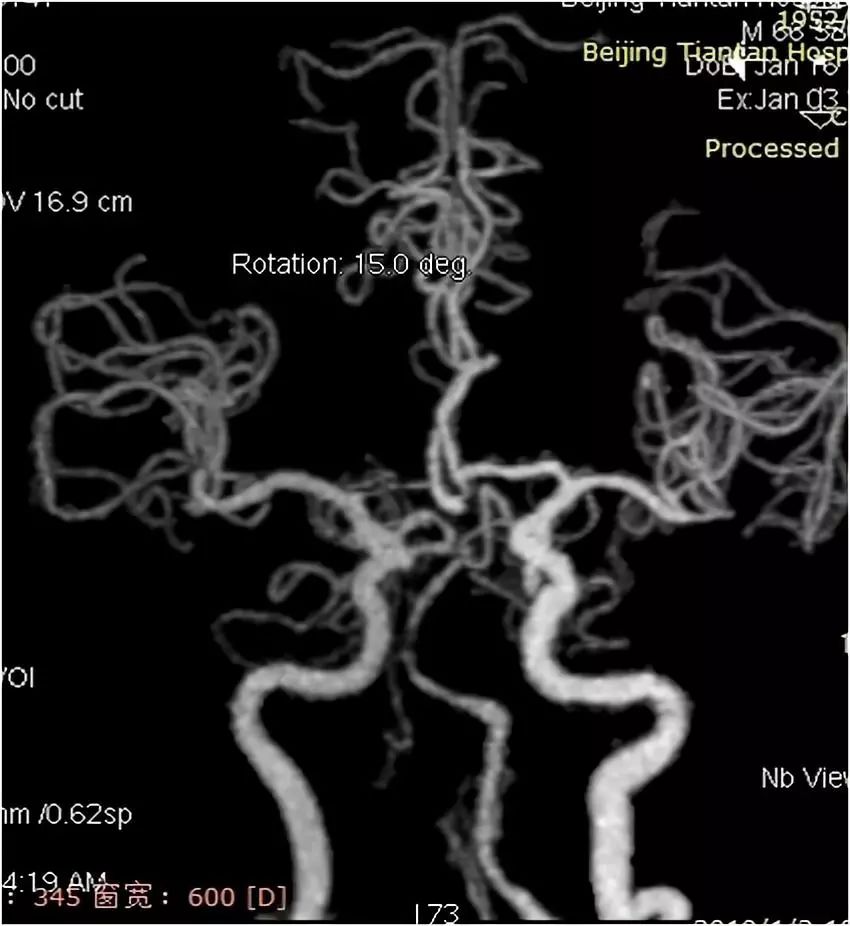

MRA:双侧胚胎型大脑后动脉;左椎动脉优势,V4段重度狭窄(图2)。

图2

术后复查头颅CTA:支架内通畅(图12)。

图12